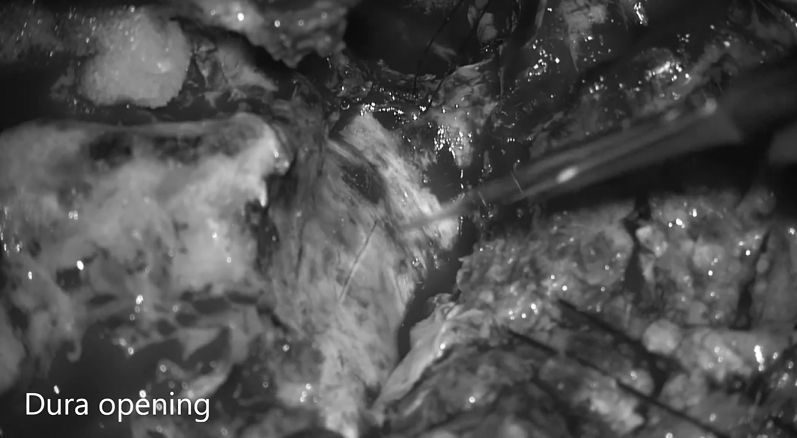

▼打开硬脑膜

▼硬膜内肿瘤切除,注意将肿瘤从脑干轻轻分离